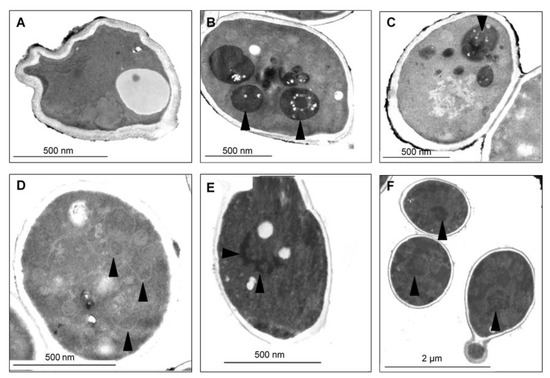

Figure 6.

(A) TEM micrographs of the control Candida tropicalis SZMC 1366 cell structure demonstrates intact membranes, small unevenly scattered condensed chromatin grains, and homogenous cytoplasm structure. (B–D) TEM micrographs of C. tropicalis treated with a sub-lethal concentration of CAPE: (B) Late-stage disintegration with membrane fingerprints, vacuolization, plasma membrane detachment (arrowheads), and vacuole formation (double arrowheads). Fine granular homogenous cytoplasm organization disappeared, and a dense, compact cytoplasm with signs of fragmentation, rounded cell shape, and whole-cell shrinkage was seen. (C) Necrotic cell with membrane ruptures (arrowheads) and loss of cytoplasm density. (D) Several peripheral vacuoles show plasma membrane involvement (arrowheads). Nuclear bleb formation (double arrowheads).